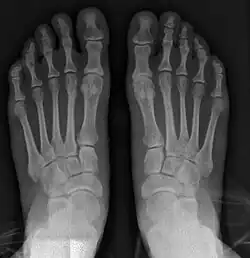

![]() Fig. 8a. Painful hallux valgus and metatarsus primus varus deformity recurrence of left foot after osteotomy surgery | |

- For recurrence correction after osteotomy procedure (Fig. 8)

Late deformity recurrence can happen after osteotomy (bone-breaking) procedures because osteotomy surgeries do not specifically stabilize first metatarsal bone.